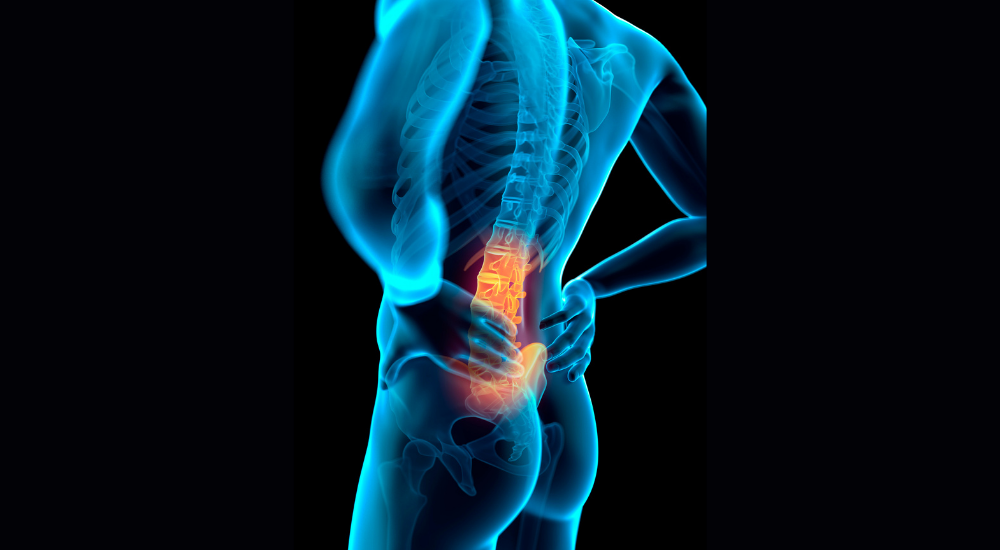

- 椎間板ヘルニア 椎間板の中身(髄核)が飛び出して神経を圧迫する疾患。腰の痛みに加え、お尻や足にかけて強い痛みやしびれ(坐骨神経痛)を伴うことが多いです。

- 脊柱管狭窄症 神経の通り道である脊柱管が狭くなり、神経が圧迫される疾患。少し歩くと足がしびれて歩けなくなり、休むとまた歩けるようになる「間歇性跛行(かんけつせいはこう)」が特徴的な症状です。

- 腰椎すべり症・分離症 腰の骨(腰椎)が前後にずれたり、骨の一部が分離したりする状態。身体を後ろに反らす動きで痛みが強くなる傾向があります。

- 仙腸関節障害 骨盤にある仙腸関節という関節の不具合によって起こる腰痛。ベルトのラインより少し下のお尻のあたりや、足の付け根に痛みが出やすいのが特徴です。

- 坐骨神経痛 お尻から太ももの裏、足先にかけて現れる痛みやしびれの総称です。多くは、椎間板ヘルニアやお尻の筋肉の硬さ(梨状筋症候群)によって神経が圧迫されることで起こります。